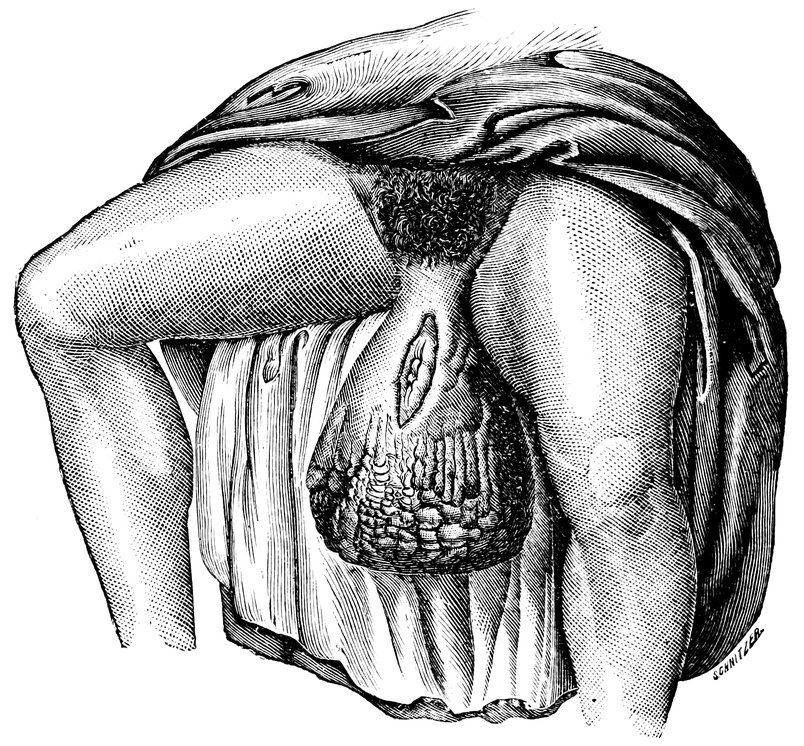

| 66. | 326 | |

| 67. | Lipoma of the Right labium majus, including the Vaginal Inlet | 328 |

| 68. | “Hottentot Apron” in an adult Woman, hanging down between the thighs (after Zweifel) | 329 |

| 69. | Elephantiasis of the Labia Majora | 330 |